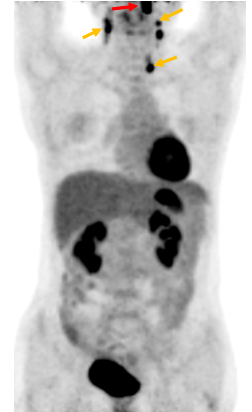

Hình 1 mô tả kết quả ghi hình PET/CT của bệnh nhân Nguyễn Th. B., nữ, 52 tuổi. Gần đây thấy xuất hiện hạch cổ hai bên. Bệnh nhân đi khám và được nội soi vòm mũi họng thì không phát hiện thấy bất thường. X-quang, siêu âm đều cho hình ảnh bình thường. Sinh thiết hạch cổ có kết quả mô bệnh học là ung thư biểu mô không biệt hóa di căn hạch. Vì vậy bệnh nhân được chỉ định chụp PET/CT để phát hiện ung thư nguyên phát. Kết quả chụp PET/CT chỉ thấy hình ảnh ung thư vòm trái, di căn hạch cổ hai bên (tổn thương u vòm nằm dưới niêm mạc thành vòm trái nên không phát hiện được khi nội soi vòm).

Hình 1: Hình ảnh tổn thương nằm dưới niêm mạc thành vòm trái tăng hấp thu FDG mạnh (mũi tên đỏ). Nhiều hạch cổ hai bên tăng hấp thu FDG (mũi tên vàng). Kết luận: Hình ảnh ung thư vòm di căn hạch cổ hai bên.